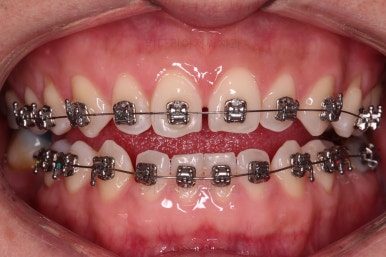

교정장치를 부착하고 충치치료는 별개로 진행되었어요.

이번에 선택하신 장치는 자가결찰(철사를 잡아주는 뚜껑이 자체적으로 달려있는) 메탈(금속)장치이며 엠파워 메탈이라고 하는 장치입니다.

세라믹에 비해 많이 보인다는 단점이 있지만 저렴하고 튼튼한 관리가 약간은 더 편하다는 장점이 있어요.

틈새는 서서히 조여서 없애주고요.

임플란트를 하기에 적절한 사이즈로 공간은 맞춰줍니다.